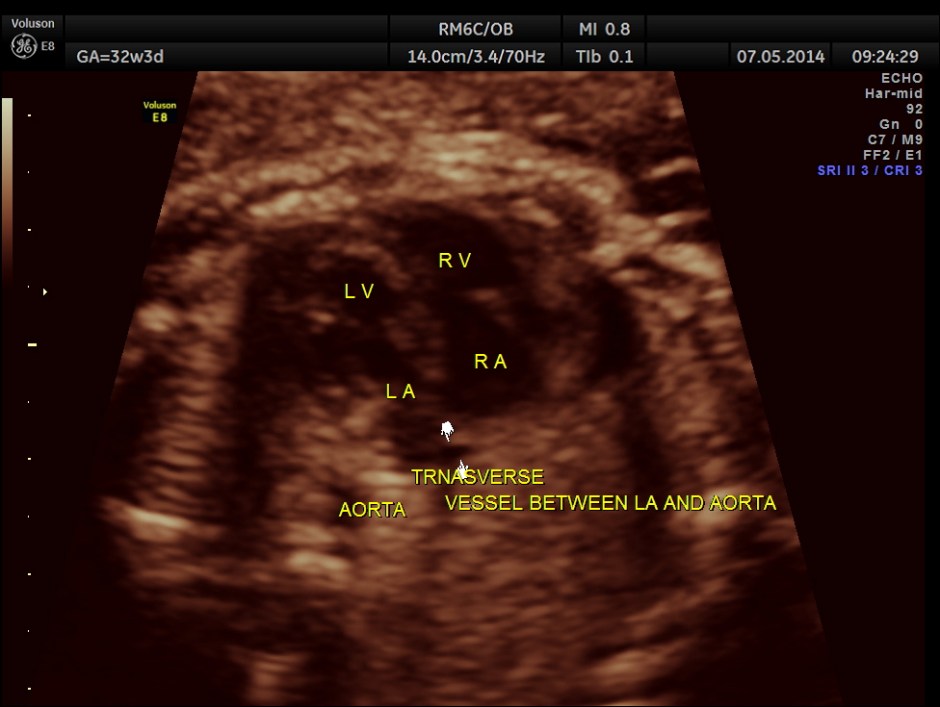

LA & LV appear to be smaller than RA & RV.

A transverse vessel is seen below the left atrium and is not seen to drain into the left atrium.

No definitive pulmonary vein draining into the left atrium could be made out . A common transverse vessel was seen beneath the left atrium . The LA & RA were smaller than the RA. Similarly the Aorta and the aortic arch were smaller than the pulmonary artery and the ductal arch due to the increased flow in the right side.